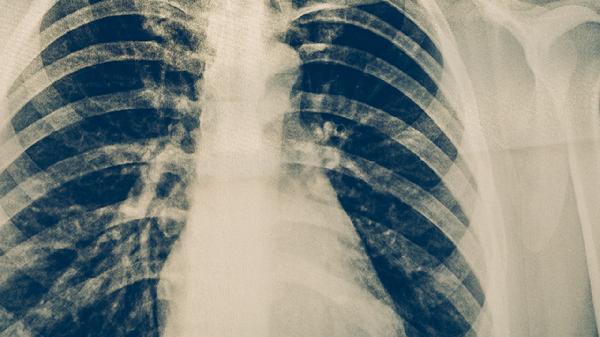

哪些人更容易患上肺结核和肺结节

肺结核和肺结节的高危人群主要包括免疫力较弱的人群、长期处于粉尘或有害气体环境中的人、患有慢性呼吸道疾病者、吸烟者,以及有家族遗传倾向的人。